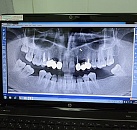

Панорамный снимок

- Показывает полную картину состояния зубов и костной ткани.

- Не требует подготовки, занимает всего 2-3 минуты.

- Обеспечивает высокое качество изображения при минимальном уровне излучения.